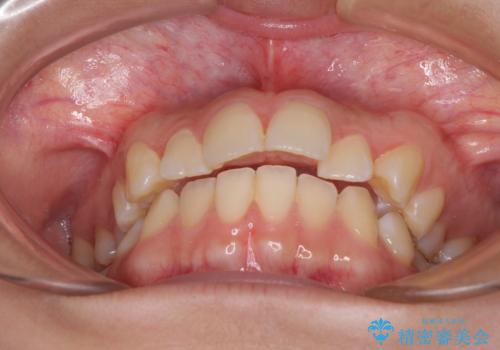

奥歯の咬み合わせを見ると、上顎が下顎に対して相対的に前方にあり、上下の前歯が接触していない状態でした。

咬み合わせを改善するためには、上顎臼歯を後方に移動させた咬み合わせにする必要があります。

インビザライン単体で改善することも可能ですが、咬合力が強く、単位で達成する可能性が低いと考えられたため、カリエール・ディスタライザーという補助装置を併用して、より確実性を上げることとしました。